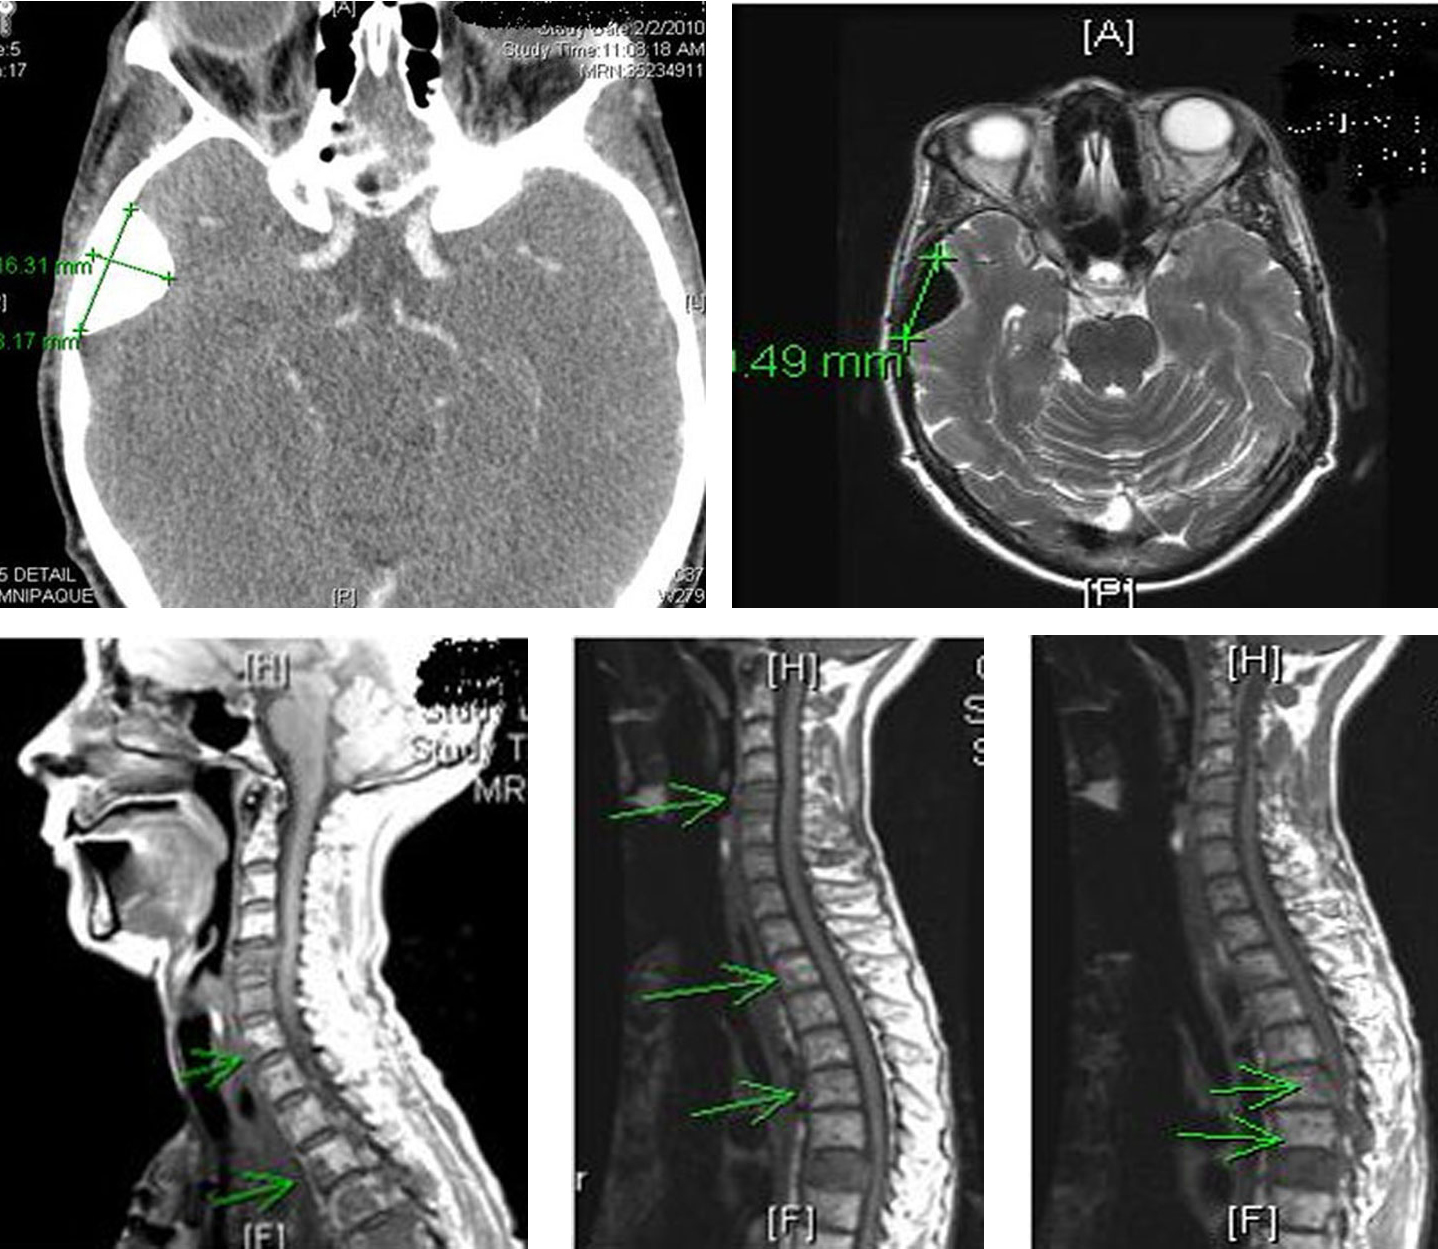

Patient received multiple cycles of chemotherapy (dacarabzine 60 mg/m2 and 5-FU 400 mg/m2), over the next 18 months. However, because of worsening lethargy, patient’s chemotherapy was stopped. Repeat computer tomography of the head and spine showed worsening spinal metastasis and metastasis to the left orbit (Fig. 10).

![]() Click for large image | Figure 10. Computer tomography of the head and spine region showing left orbital metastasis and worsening spinal metastasis. |